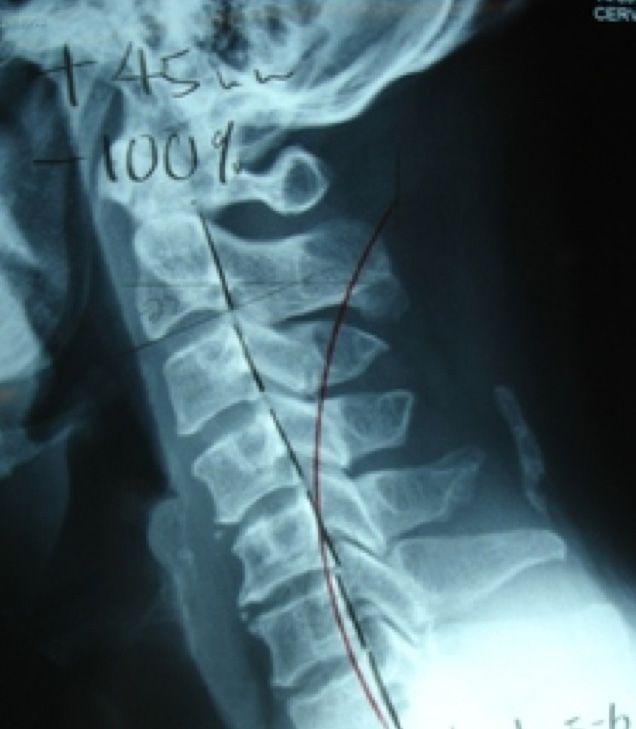

Phase I Cervical Spine

Loss of normal curves and nervous system dysfunction result from uncorrected spinal trauma.

Usually seen as the misalignment and malfunction of the spine. Normal spinal motion, curves & disc spacing are altered. Because the body is so adaptable, this early phase can exist without warning of pain or other symptoms. If left uncorrected, the degeneration continues.